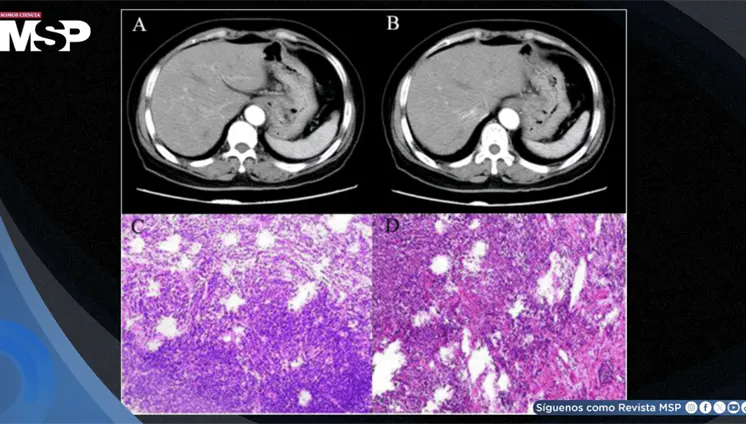

El estudio histológico confirmó un adenocarcinoma mucinoso de células en anillo de sello de vejiga con invasión muscular y diseminación metastásica pulmonar y ósea.